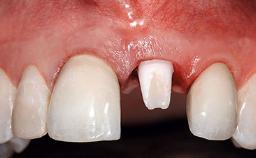

Replacement of a Compromised Upper Right Central Incisor: Hard- and Soft-tissue Augmentation, Late Placement of an RC Bone Level Implant

A 36-year-old male patient with a compromised maxillary central incisor was referred by his general dentist for consultation. The patient’s chief complaints were the gradual debonding of a temporary crown on the right central incisor and unsatisfactory esthetics due to an increasing diastema between the right central and lateral incisors. The patient reported a traumatic event some years previously, when a crown had been placed after root-canal treatment. The referring dentist wanted to provide a new crown restoration, but was concerned about the condition of the residual root. Anamnesis was negative for any other dental or periodontal pathology in the remaining dentition. The patient reported taking no medications: He was a smoker (10 to 15 cigs/day) and had realistic esthetic expectations.